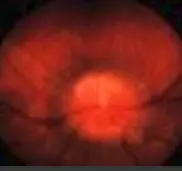

The optic disc initially appears hyperemic and swollen.